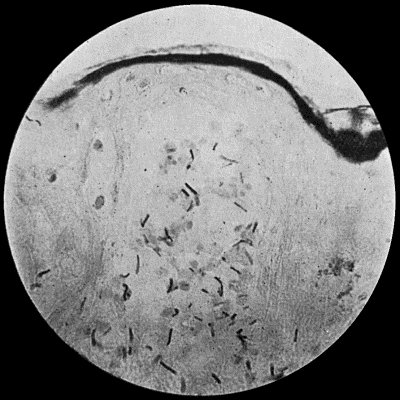

| 2. | Staphylococcus aureus in Pus from case of Osteomyelitis | 25 |

Staphylococcus Aureus.—This is the commonest organism found in localised inflammatory and suppurative conditions. It varies greatly in its virulence, and is found in such widely different conditions as skin pustules, boils, carbuncles, and some acute inflammations of bone. As seen by the microscope it occurs in grape-like clusters, fission of the individual cells taking place irregularly (Fig. 2). When grown in artificial media, the colonies assume an orange-yellow colour—hence the name aureus. It is of high vitality and resists more prolonged exposure to high temperatures than most non-sporing bacteria. It is capable of lying latent in the tissues for long periods, for example, in the marrow of long bones, and of again becoming active and causing a fresh outbreak of suppuration. This organism is widely distributed: it is found on the skin, in the mouth, and in other situations in the body, and as it is present in the dust of the air and on all objects upon which dust has settled, it is a continual source of infection unless means are taken to exclude it from wounds.

Fig. 3.—Streptococci in Pus from an acute abscess in subcutaneous tissue. × 1000 diam. Gram's stain.